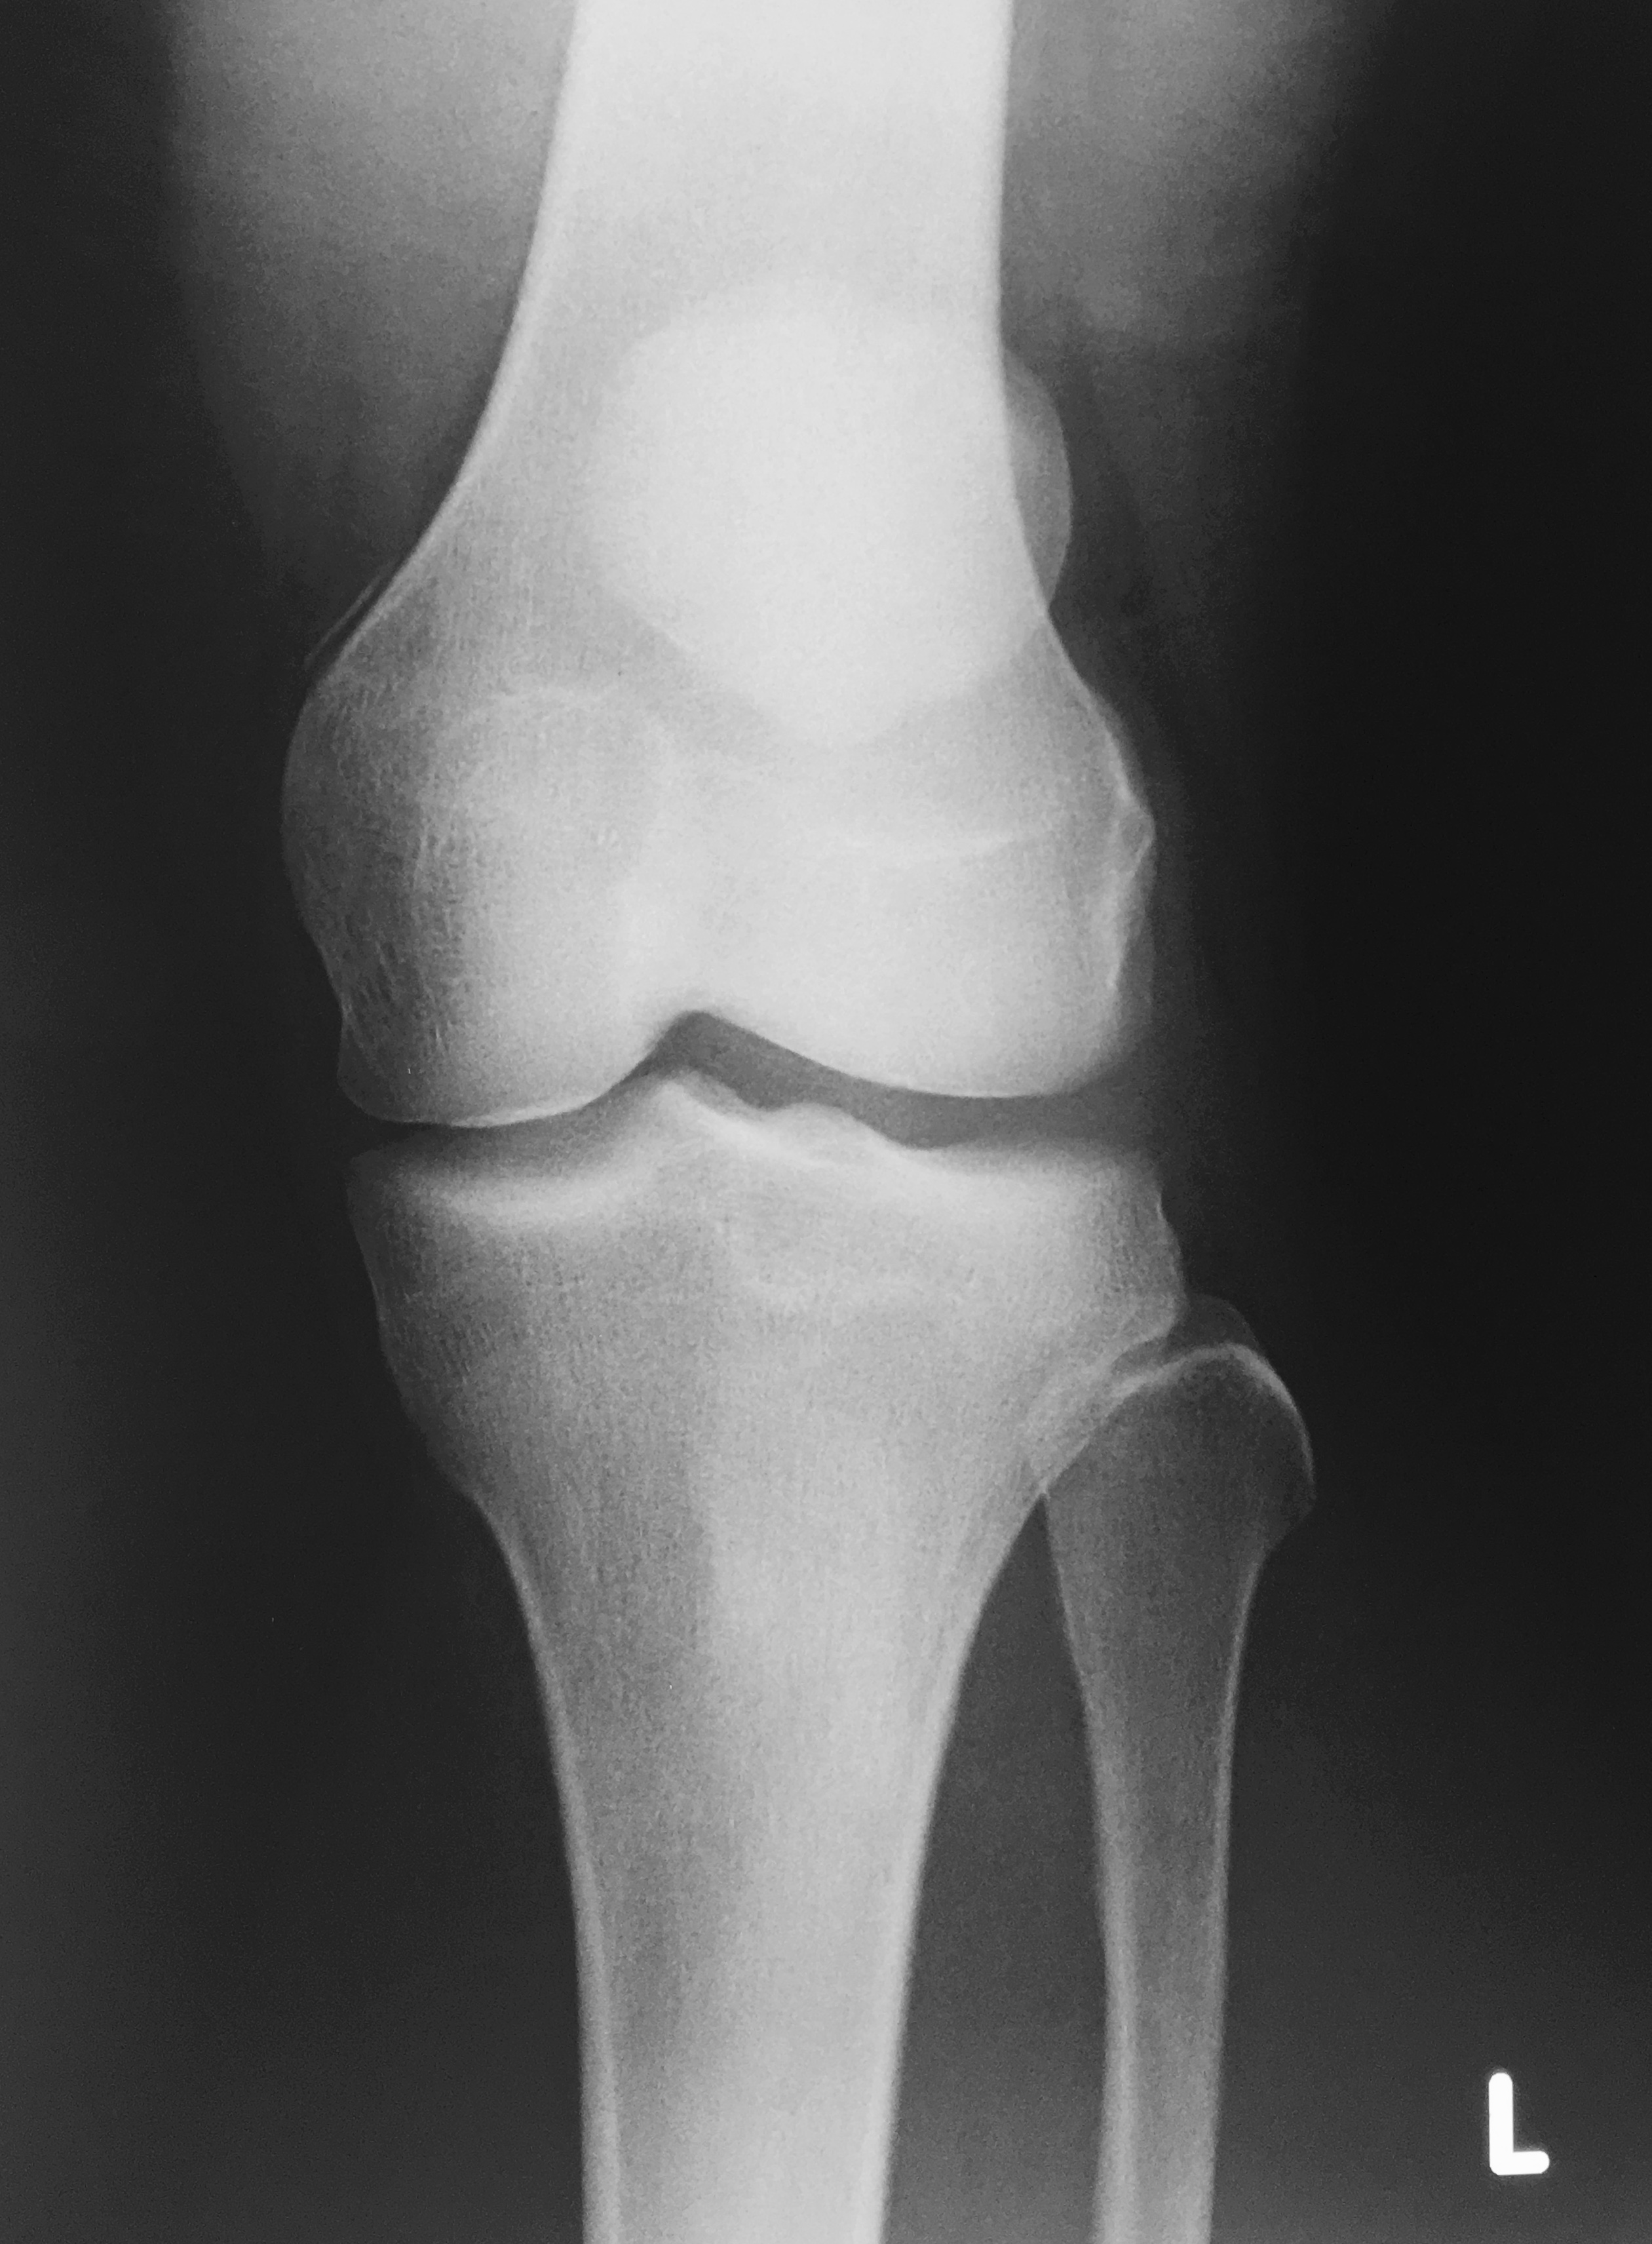

Медицинские снимки: рентген коленного сустава при остеопорозе